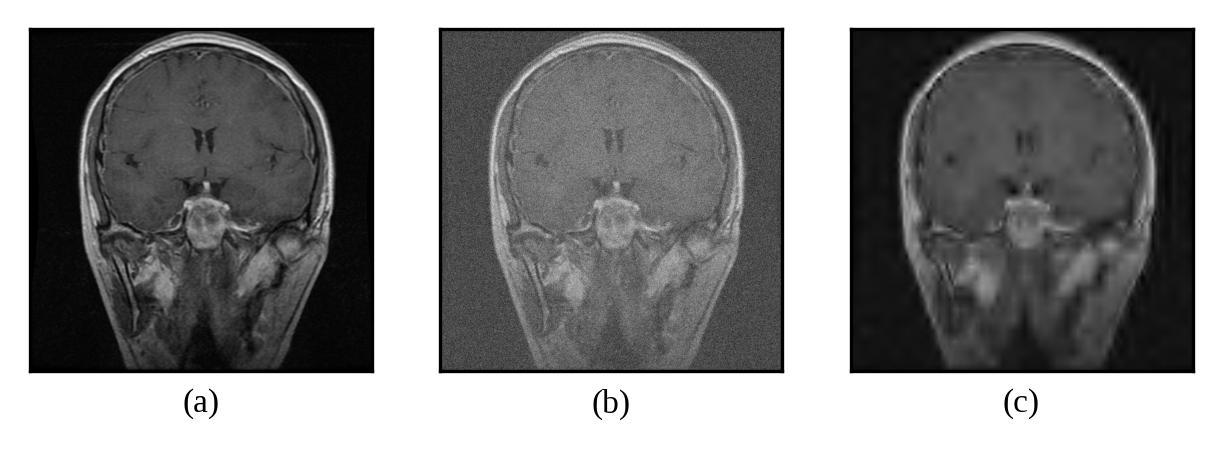

Representative denoising results are illustrated in Figures 2 through 7, demonstrating the visual improvement achieved by both thresholding methods across different noise levels.

Figure 4: (a) Original Image, (b) Noisy Image(μ=0\mu=0, σ=15\sigma=15), (c) Denoised Image (with threshold value τbayes\tau_{bayes})

Refer to caption